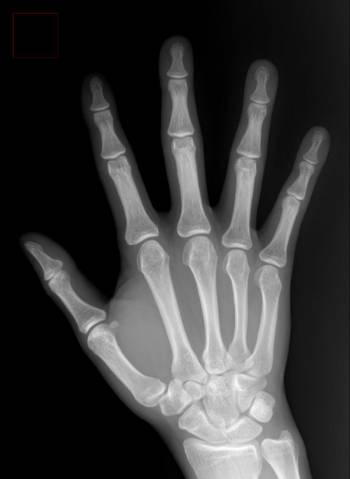

실제 목디스크 환자는 직접적인 목 통증보다 어깨나 팔 등 다른 곳에서 증상이 시작되는 사례가 많다. 목덜미나 어깨 위쪽의 통증이 가장 흔하고 팔과 어깨 저림, 손가락 끝까지 저림이 타고 내려오는 증상이 나타나기도 한다. 심한 경우 척수 손상으로 다리의 힘이 약해지거나 마비가 발생하기도 한다.

수근관증후군과 목디스크는 치료법이 다른 만큼 병을 혼동하거나 잘못된 치료를 했다간 원인 질환을 더 악화시킬 수 있다. 이 경우 먼저 근전도 검사를 통해 손 저림의 원인이 목디스크인지, 손목터널증후군인지 확인해야 한다. 소요 시간이 짧고 검사법도 간편하다.